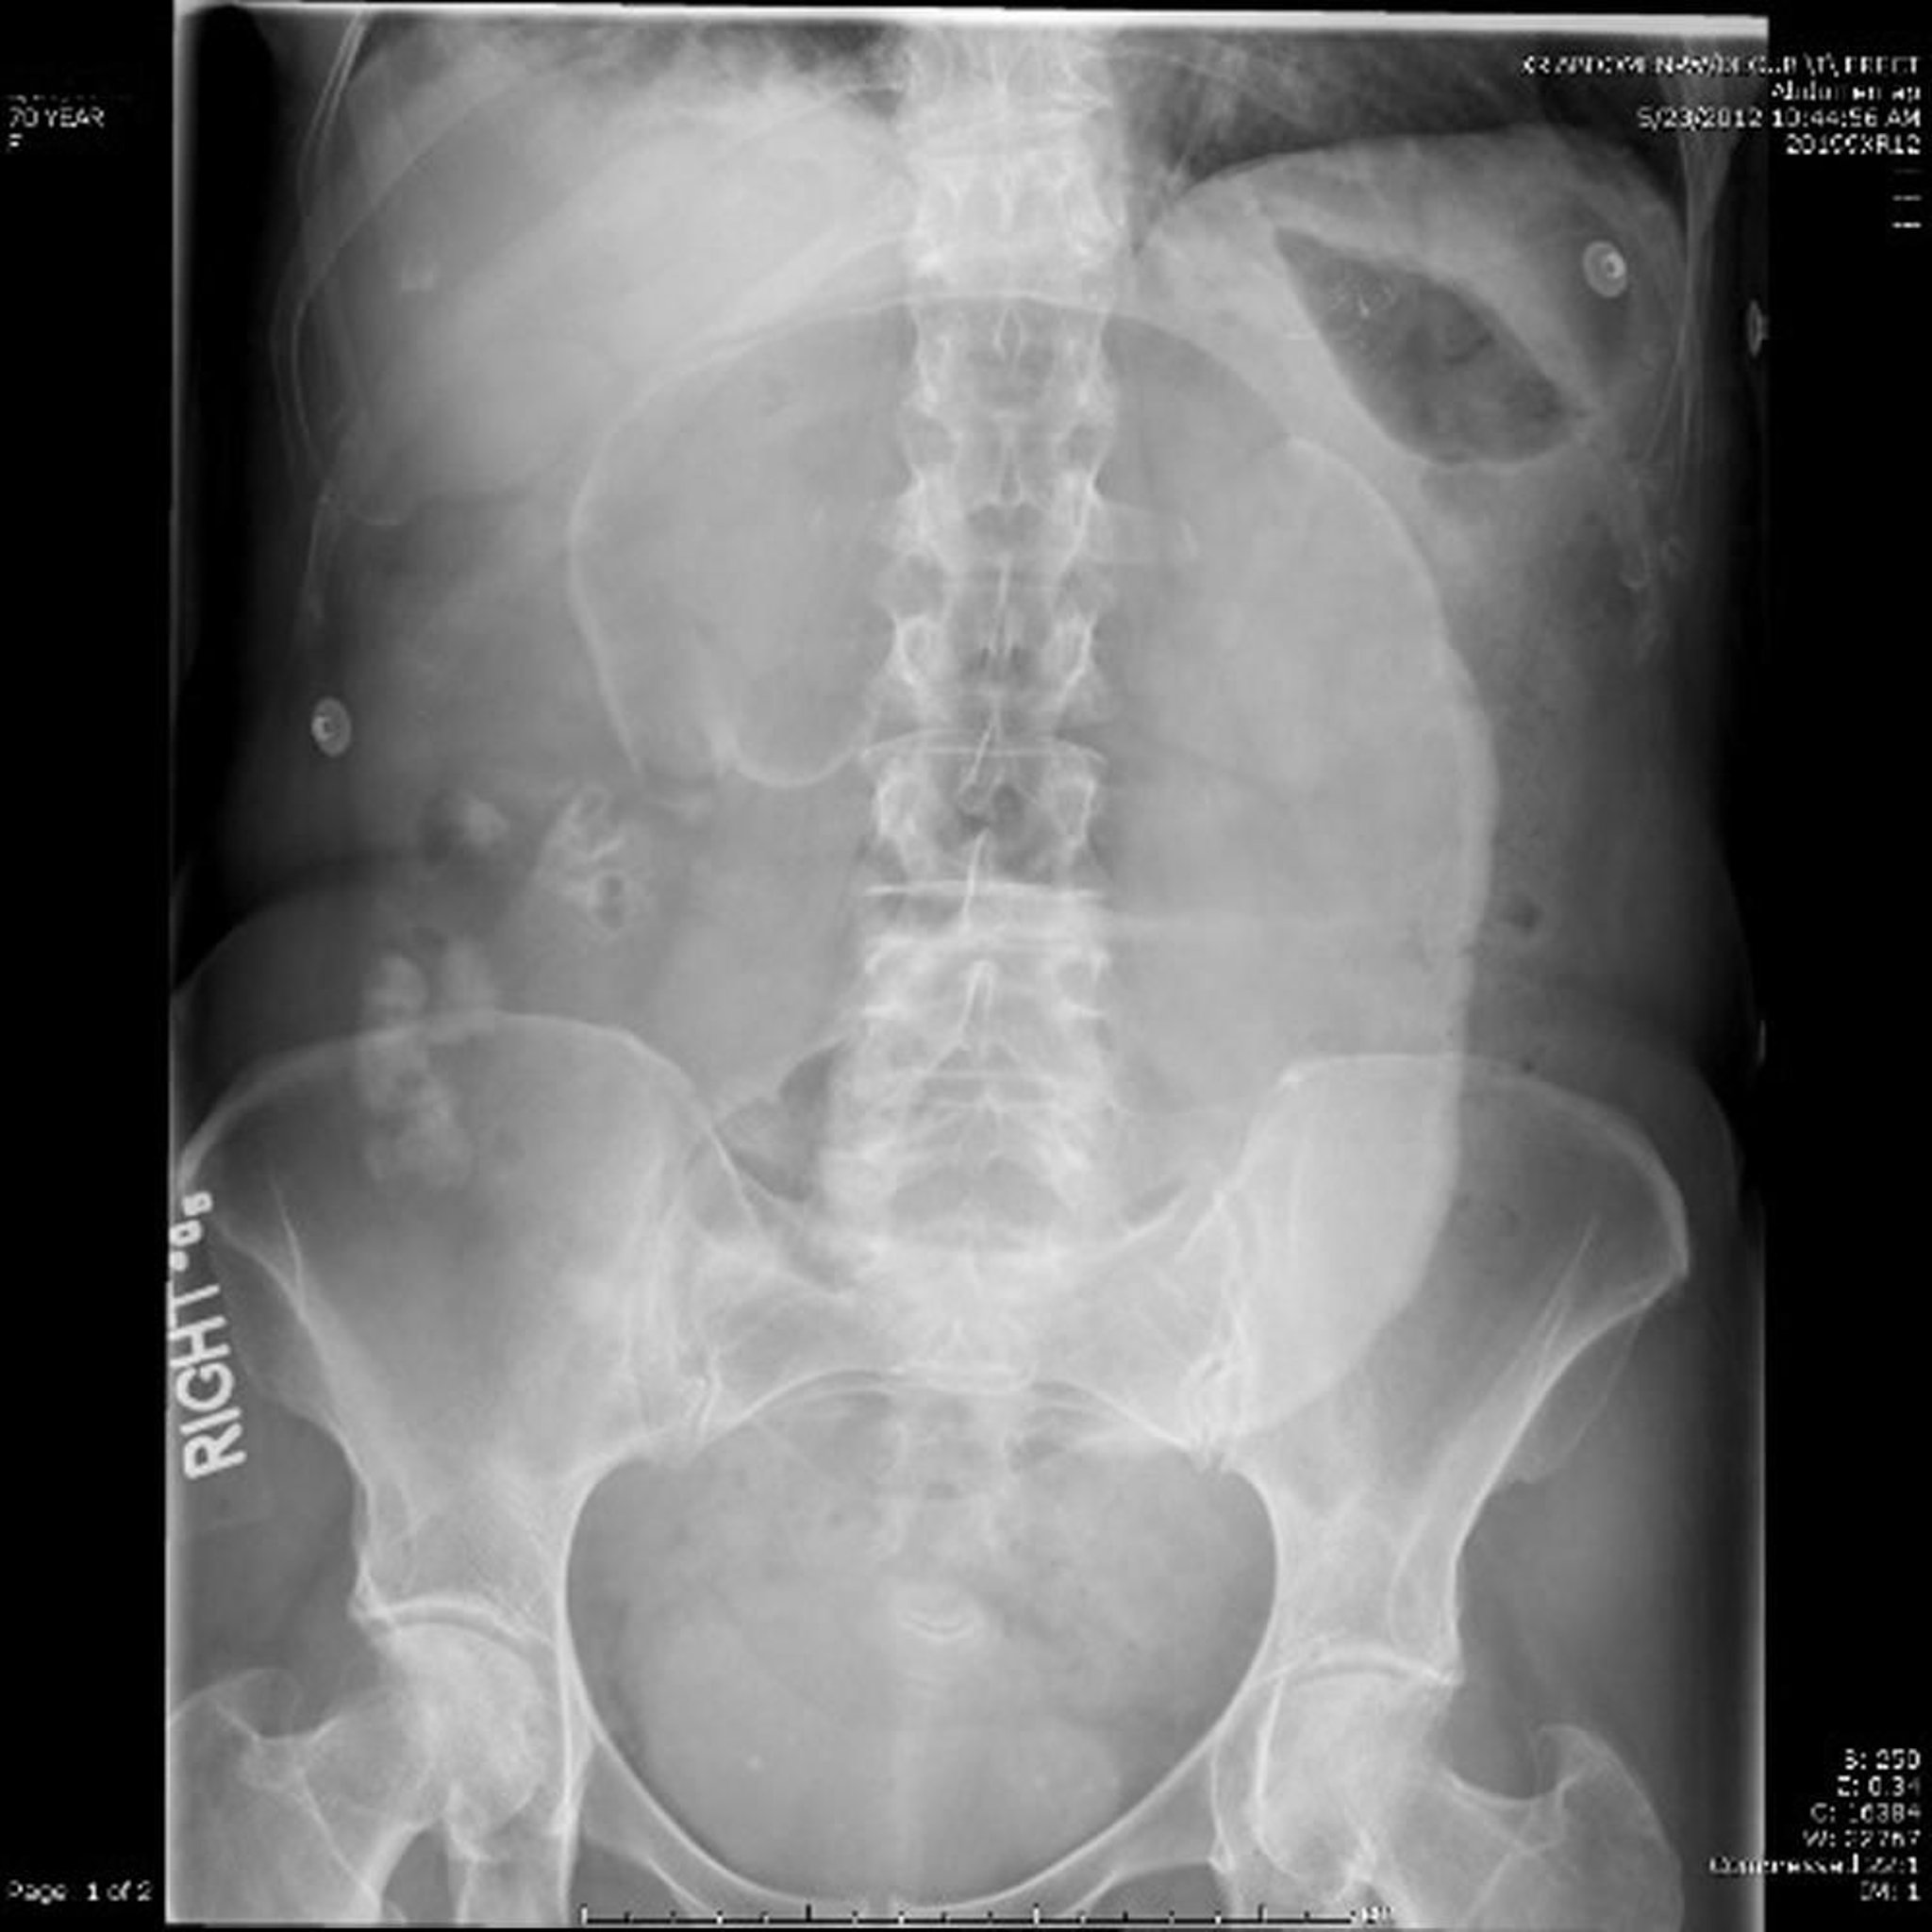

Volvolo cecale (RX addominale)

Alla RX addominale, il cieco è attorcigliato attorno al suo mesentere, facendo sporgere un "chicco di caffè" dilatato verso il quadrante superiore sinistro.

Image provided by Parswa Ansari, MD.